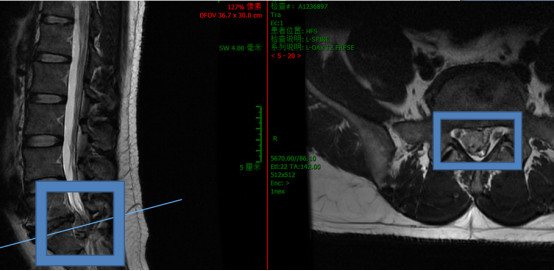

腰5-骶1椎间盘巨大脱出

髓核掉入椎管内压迫马尾神经

报告显示,腰5/骶1椎间盘变性并膨出,伴右后下脱出,椎管狭窄。腰5-骶1椎体终板炎。

何升华主任根据检测报告,帮我仔细检查后分析我的情况是腰椎间盘突出引起马尾神经损伤,正是马尾综合征。